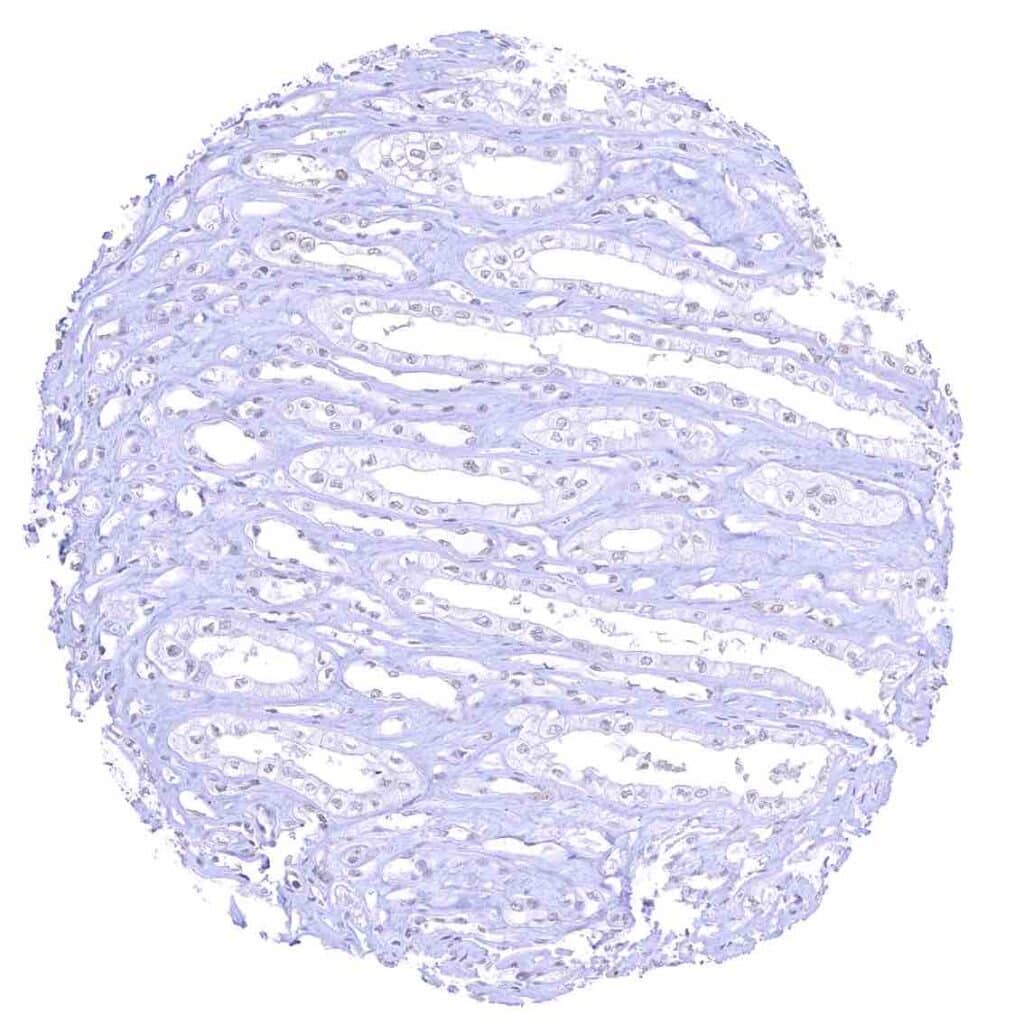

Urinary bladder, muscular wall